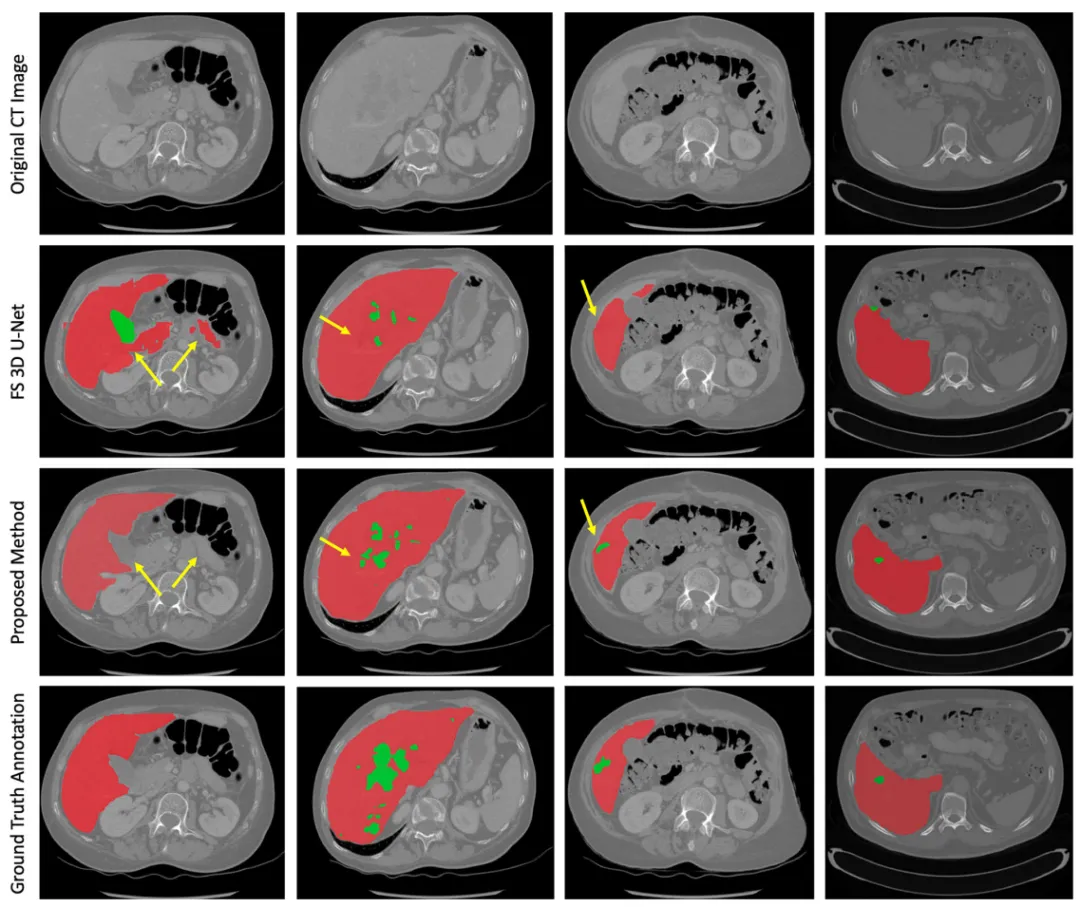

视觉对比验证了本文方法在分割质量上的显著优势,有效避免了传统方法的过度分割、小肿瘤漏检等错误。其生成结果与金标准高度一致,边界清晰度和解剖结构保持优异,为临床手术规划和疗效评估提供了可靠依据(图3)。

图3.代表性案例的可视化分析